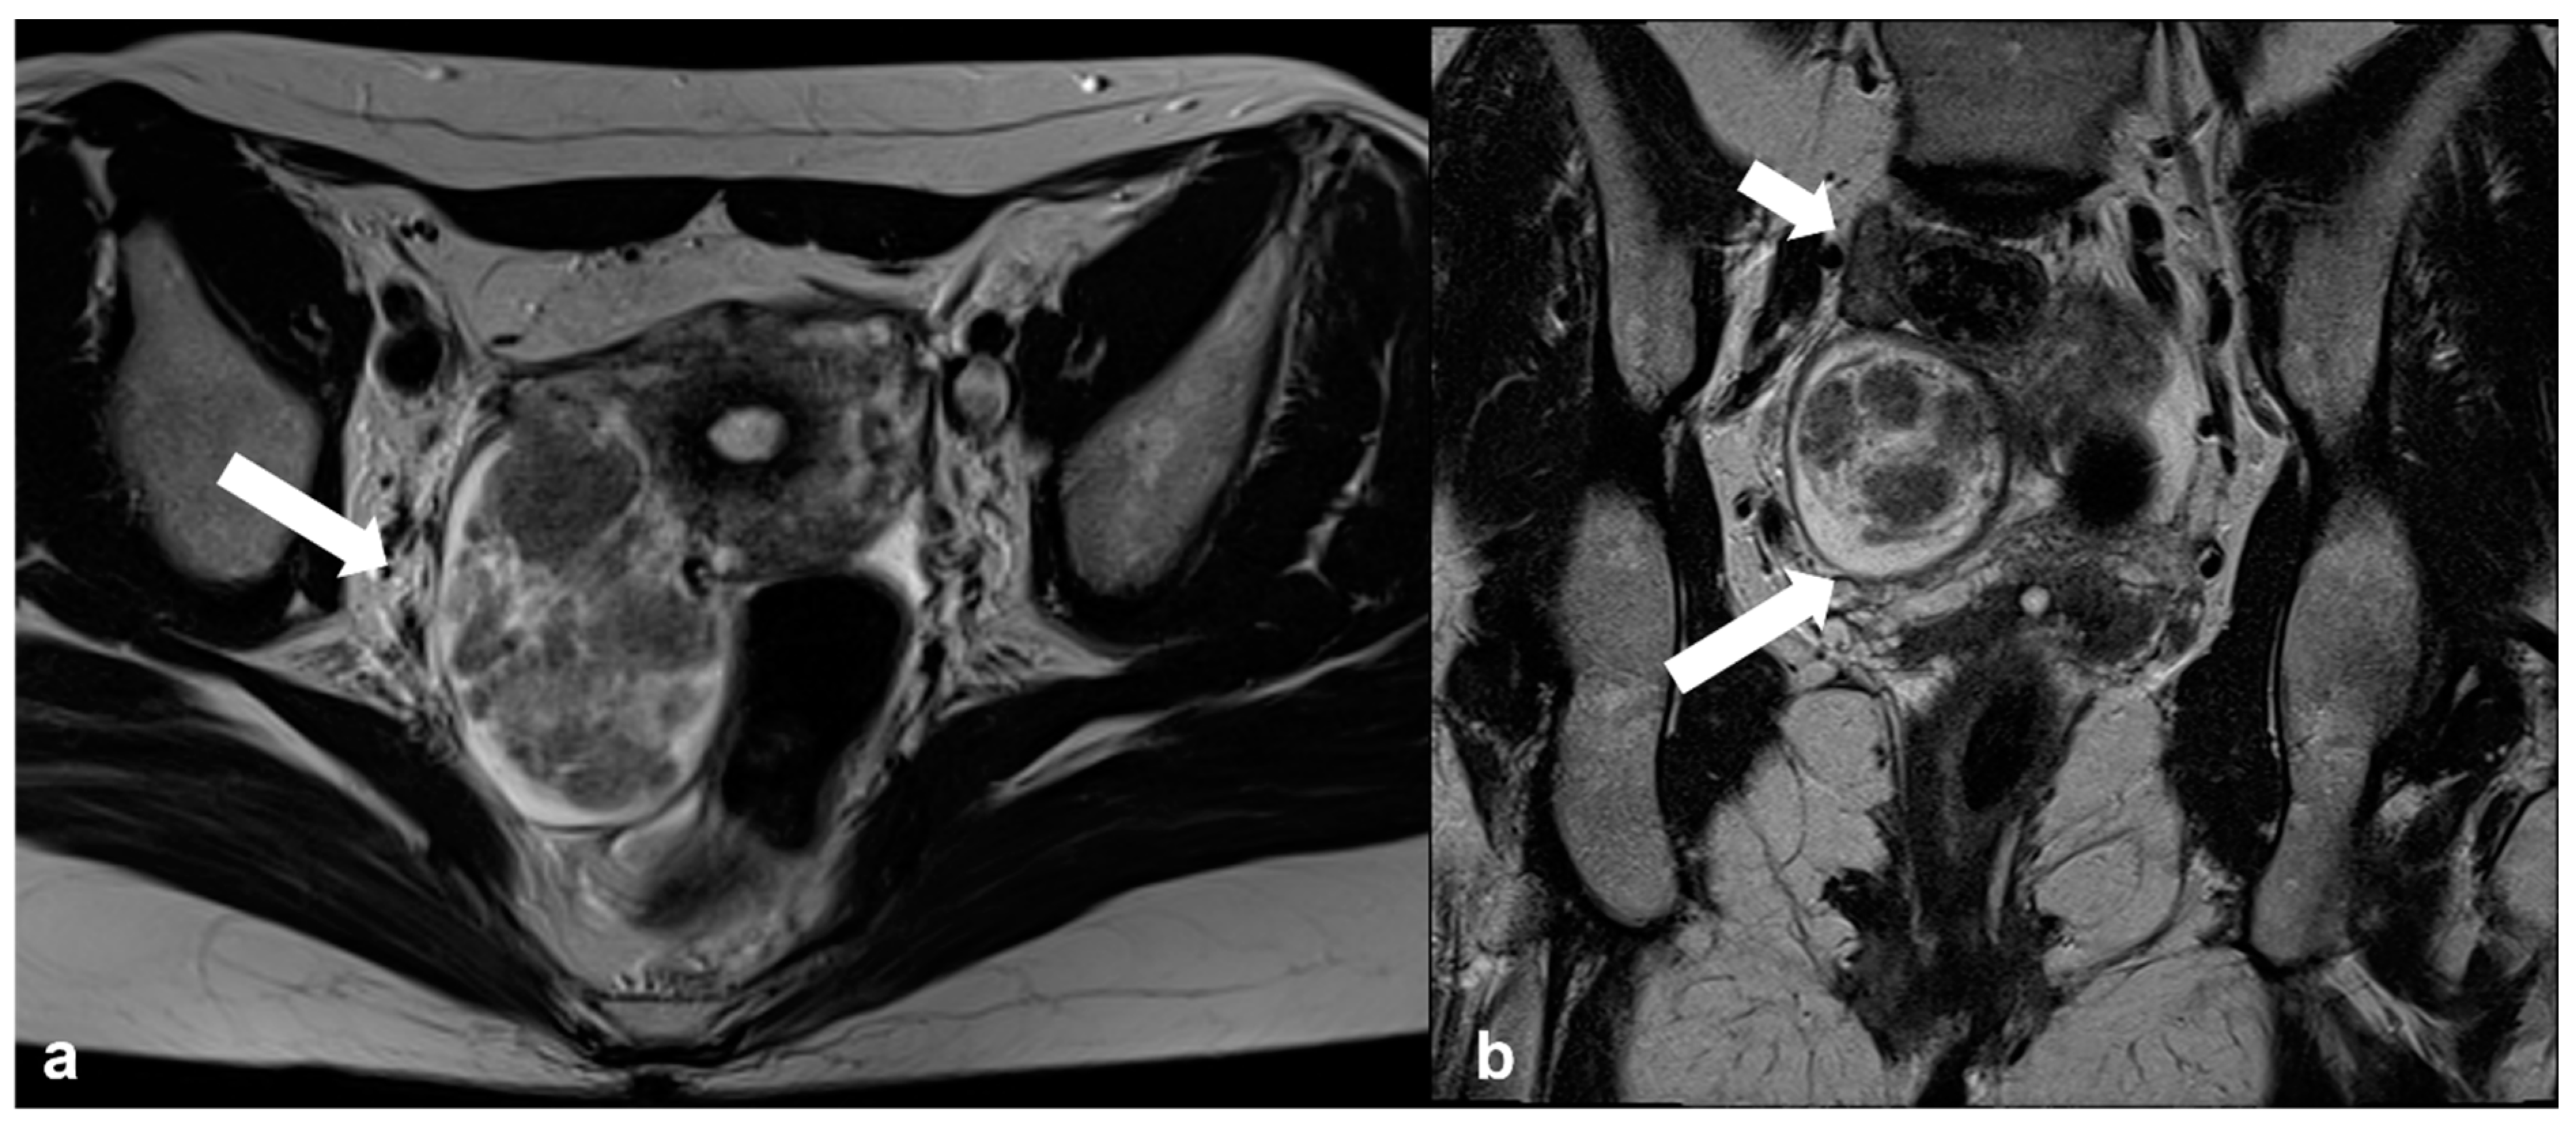

2.1.1. High-Grade Serous Cystadenocarcinoma (HGSC)

2.1.4. Endometrioid Carcinoma and Clear Cell Carcinoma